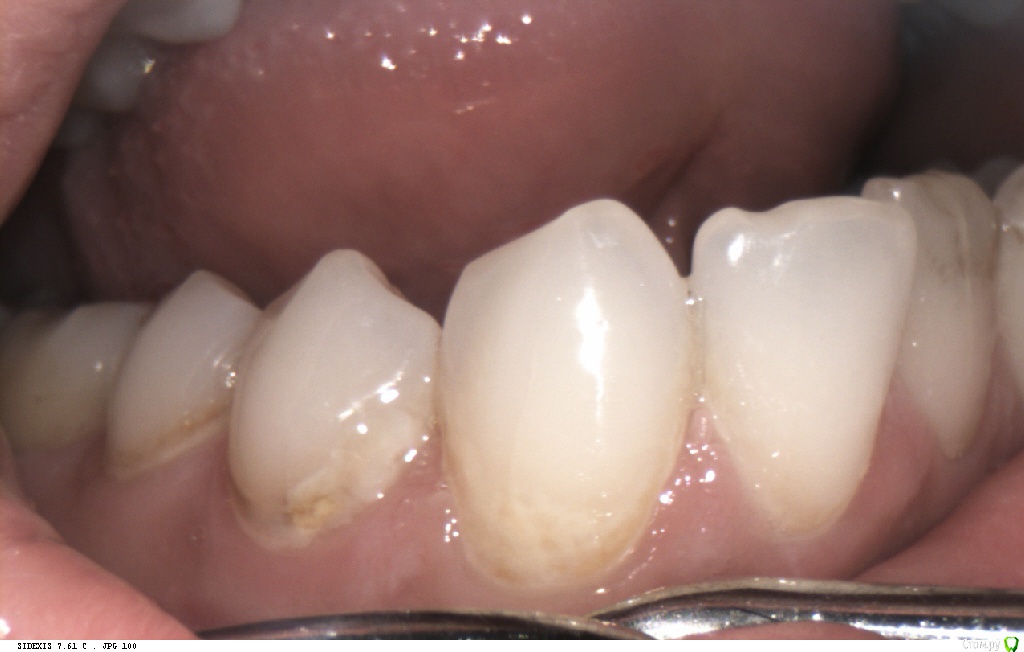

Pan Опубликовано 6 мая, 2017 Поделиться Опубликовано 6 мая, 2017 (изменено) типичная локализация кариеса при плохой гигиене и злоупотреблении в питании фастфуда. Ну понятно, что всё это на фоне сниженной кариесрезистентности. Первым делом нужно объяснить девушке значимую роль питания и гигиены в развитии кариозных процессов. Изменено 6 мая, 2017 пользователем Pan 1 Ссылка на комментарий

St. Опубликовано 9 мая, 2017 Поделиться Опубликовано 9 мая, 2017 Принесла анализы и заключения специалистов.как оказалось пару месяцев назад обследовалась. Практически космонавт)) Слегка увеличена щитовидка, но гормоны в норме. Газировку и фреши не пьет, фастфуд не ест. Так ничего не беспокоит кроме внешнего вида.Озвучили вариант терапевтического лечения сиц+рем.терапия ивариант тотала, ушла думать.Как думаете тотал может решить вопрос или есть высокая вероятность вторичного поражения? Ссылка на комментарий

Pan Опубликовано 11 мая, 2017 Поделиться Опубликовано 11 мая, 2017 (изменено) Деструкция эмали (в типичных для зубного налета местах) произошла значительно ранее ( разве нужно еще раз говорить об истинных причинах, способствующих этому процессу?) Потом, конечно, индивидуум (взрослея) изо всех сил старается и отсутствие признаков гингивита(если хотите) тому подтверждение. Но, увы, процесс уже запущен... Вы конечно же не хотите оспорить тот факт, что деструкцию эмали (кариес) вызывают бактерии зубного налета. Изменено 11 мая, 2017 пользователем Pan Ссылка на комментарий